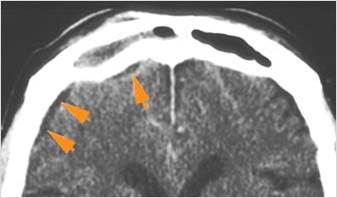

There is a subperiosteal fluid collection or abscess along the boney walls of the anterior or middle cranial fossa.

There is an epidural fluid collection or abscess along the boney walls of the anterior or middle cranial fossa.